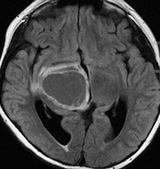

放射線治療前

若い男性です。ある病院で生検術が行われたのですが病理診断がはっきりしませんでした。強度変調放射線治療 IMRT 54グレイ・27分割の放射線治療を行いました。左大脳基底核の乏突起膠腫系腫瘍と考えられたので,増強病変外マージンは10mmととても狭い領域で46グレイ・23分割と低い線量に押さえられています。テモダール 75mg/m2を放射線治療期間中に併用しています。左はガドリニウム増強MRI,右はFLIAR(フレア) 画像。